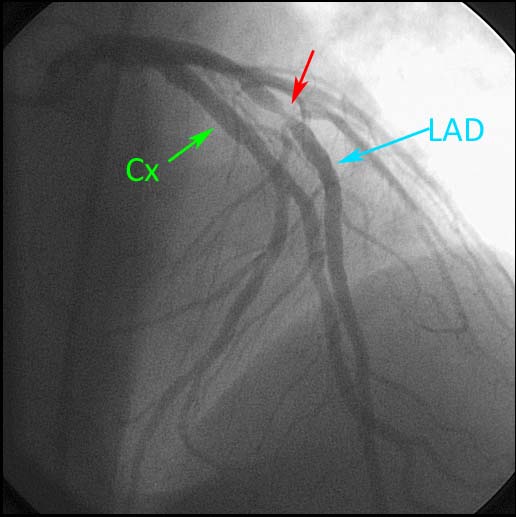

Kırkbeş yaşında erkek hasta acil servisimize yaklaşık 1 saat önce başlayan, göğsün orta hattından sol kola yayılan baskı tarzında ağrı ve halsizlik şikayetiyle başvurdu. Hasta yaklaşık beş gündür aralıklarla gelen göğüs ağrısından şikayet etmekteydi. Şikayetleri ilk başladığında bir dış merkeze başvuran hastanın kardiyak enzimleri normal saptanırken, EKG’de V1,V2’de bifazik T dalgaları, V3-V4’te derin, ters T dalgaları gözlemlenmiş(şekil1). Gözlem sonrası şikayetleri tamamen geçen hasta kardiyoloji poliklinik kontrolü önerilerek taburcu edilmiş. Hastanın hikayesinde 10 paket/yıl sigara kullanımı mevcuttu. Diabet, hiperlipidemi, hipertansiyon ve ailesinde koroner arter hastalığı öyküsü yoktu. Acil serviste yapılan fizik muayenesinde nabız dakika sayısı 105/dk, tansiyon arteriyel 130/80mmHg, vücut sıcaklığı 36 ºC, solunum sayısı 14/dk, oda havasında oksijen satürasyonu %98 idi. Kardiyovasküler ve diğer sistem muayeneleri normaldi. EKG’de ritim, normal sinüs ritmi, 110/dk hızında olup V1-V6 derivasyonları arasında 2 mm ST segmenti elevasyonu mevcuttu. Hasta bu bulgularla kardiyoloji ekibi tarafından anterior MI tanısı ile primer perkütan girişim için kateter laboratuvarına alındı. Yapılan koroner anjiografide (şekil 2) sol ana koroner arter (LMCA): normal, LAD proximalinde tama yakın tıkanıklık saptandı ve LAD’ye stent implante edildi. İşlem sonrası hastanın göğüs ağrısı geçmiş, ST segment elevasyonunda %70 azalma gözlenmiş olarak saptandı. Servis izlemleri problemsiz seyreden ve kardiyak belirteçleri normal değerlere gerileyen hasta tikagrelor, aspirin, atorvastatin ve bisoprolol tedavileriyle taburcu edildi.

Şekil 2. LAD proksimalinde tama yakın tıkanıklığı gösteren koroner anjiyografi görüntüsü